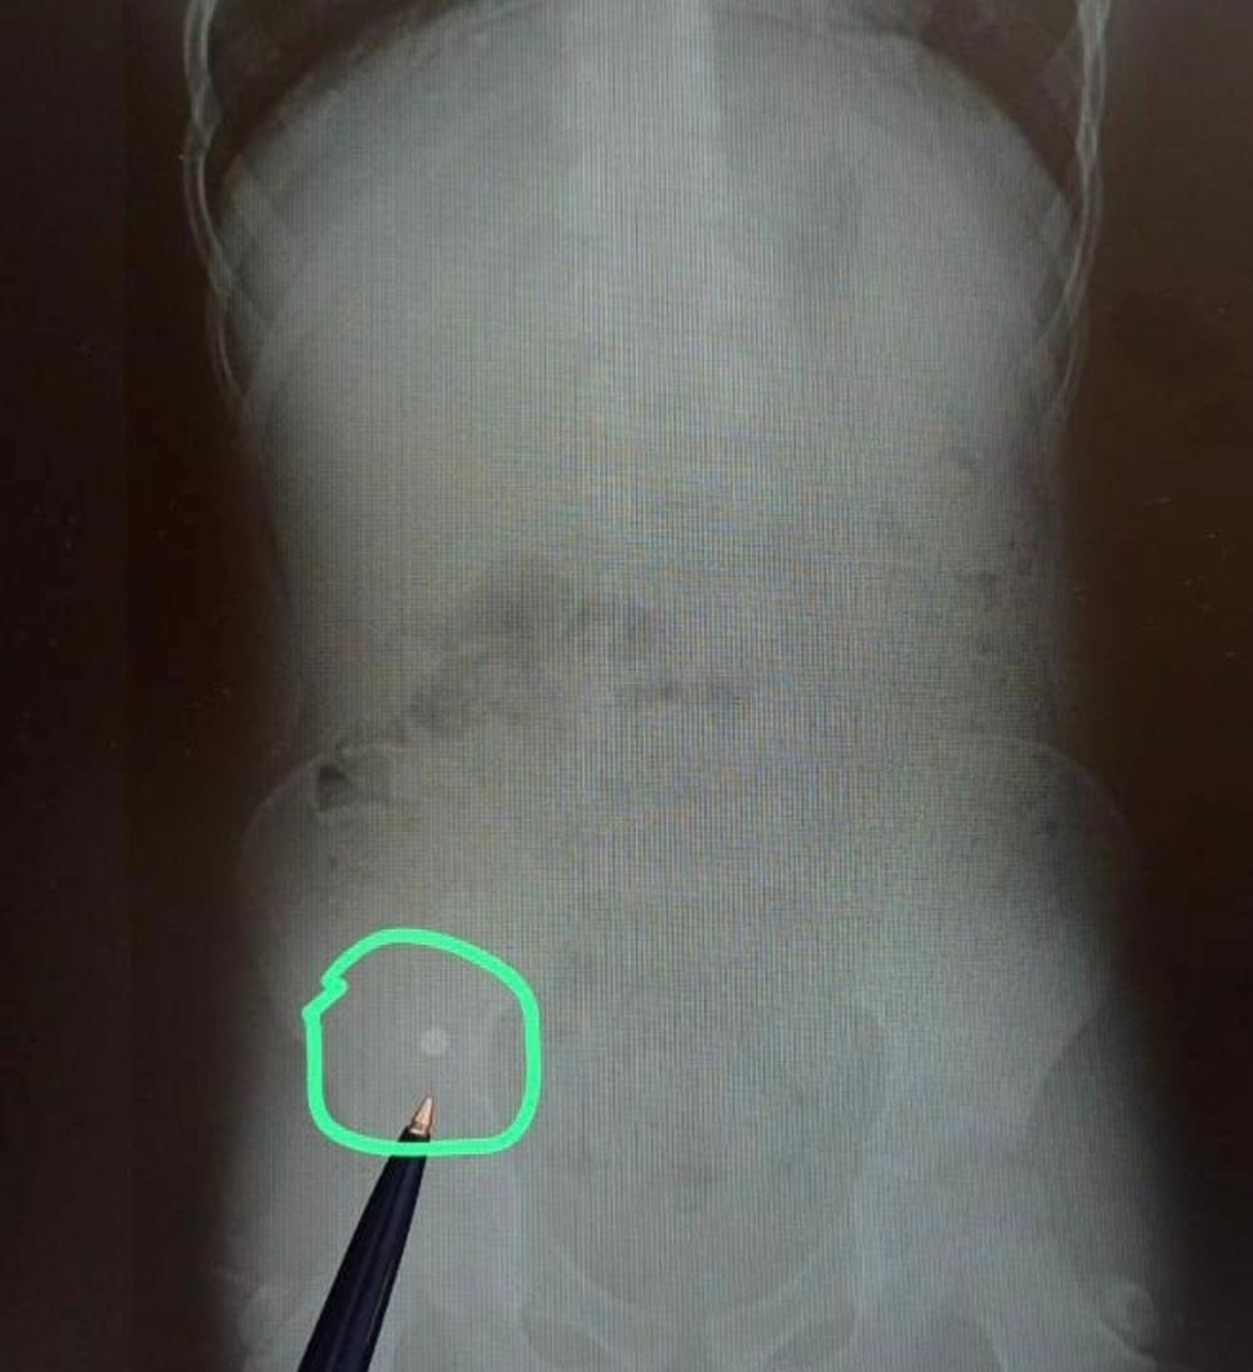

В апреле в уфимскую детскую клиническую больницу № 17 поступил семилетний мальчик, который проглотил шарики от магнитного конструктора. При рентгенографии желудочно-кишечного тракта были выявлены две тени округлой формы, соединенные между собой диаметром 5 мм, предположительно, в куполе слепой кишки. Хирургическая бригада провела экстренную операцию: магнитные шарики были успешно извлечены. Врачи использовали менее травматичный оперативный метод: не вскрывая просвет кишечника, при помощи пальцев переместили инородные тела в червеобразный отросток и провели аппендэктомию. Если бы магниты оказались в разных петлях кишечника, то произошла бы перфорация кишечника и каловый перитонит, что очень опасно для жизни.